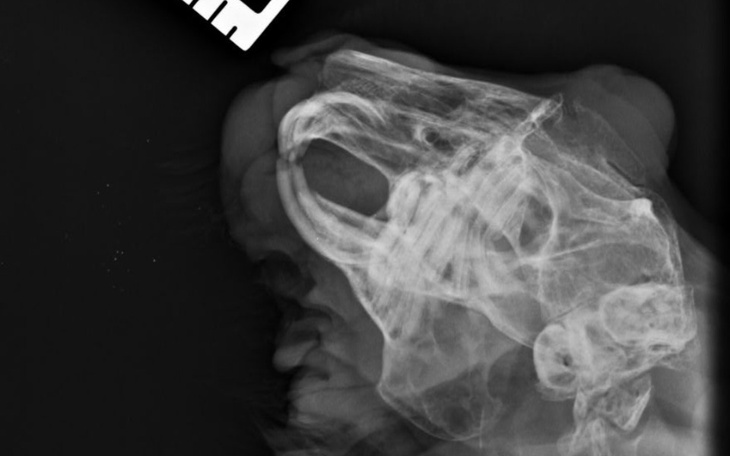

Po przebytych badaniach i zdobieniu zdjecia rtg Pani Dr zauważyła, że Tuptus ma problemy stomatologiczne, a jeden z zębów zaczął rosnąć Tuptusiowi w górę, jeszcze trochę a wrósł by mu w oko.. Dlatego tez Tuptus musi przejsc zabieg usuniecia conajmniej trzech zębów (jeden na górze, dwa na dole), ktore sprawiają mu ogromny bol, jest tez ryzyko, ze straci oko pod ktorym znajduje się ząb..